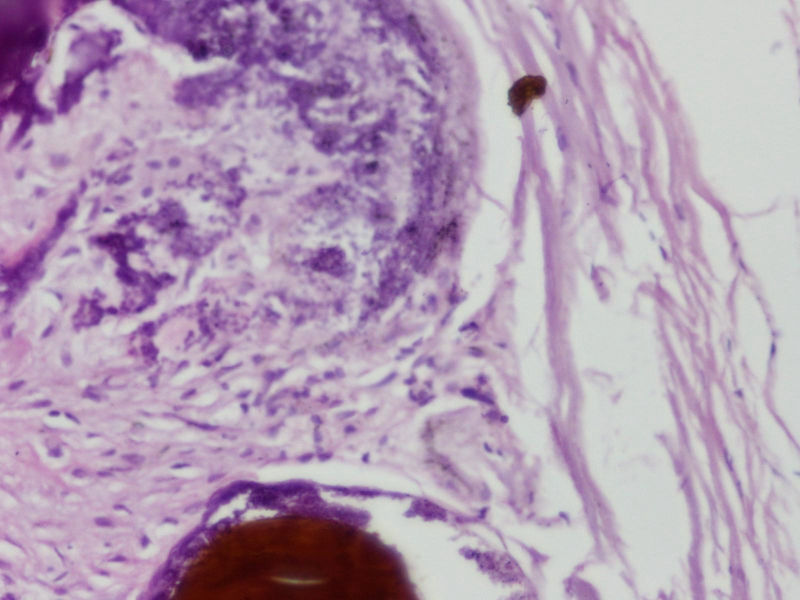

网膜结节

图1

图2

图3

图4

图5

图6

图7

图8

图9

图10

寄生虫卵?

应该是钙皂,有无慢性胰腺炎?